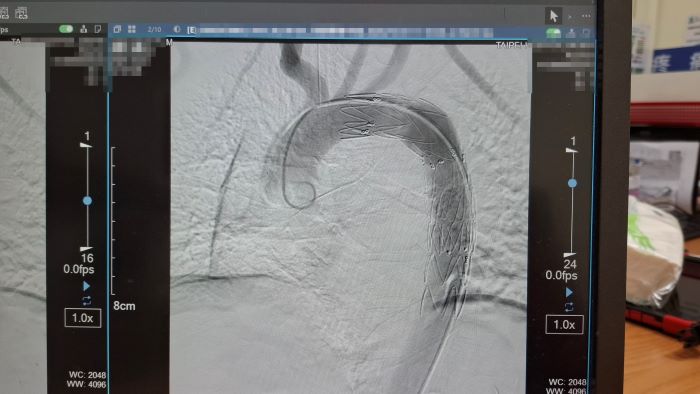

院方緊急會診心臟血管外科醫師孟繁傑,評估後立即施行「胸主動脈腔內血管支架置放手術」,僅在腹股溝處開出不到1公分的小傷口,將支架透過導管送入主動脈破裂處封堵出血點,成功解除致命危機。廖先生術後恢復順利,目前已平安出院。

孟繁傑表示,近年來,主動脈腔內血管支架置放手術逐漸成為主流治療方式。醫師只需從腹股溝股動脈置入導管,將金屬支架精準送到破裂位置撐開血管並封住破口,不僅傷口小、手術時間短,也能降低出血與併發症風險。目前此項治療方式已被美國血管外科學會列為主要治療建議,台灣健保也已納入給付,讓患者能以較低負擔接受先進治療。